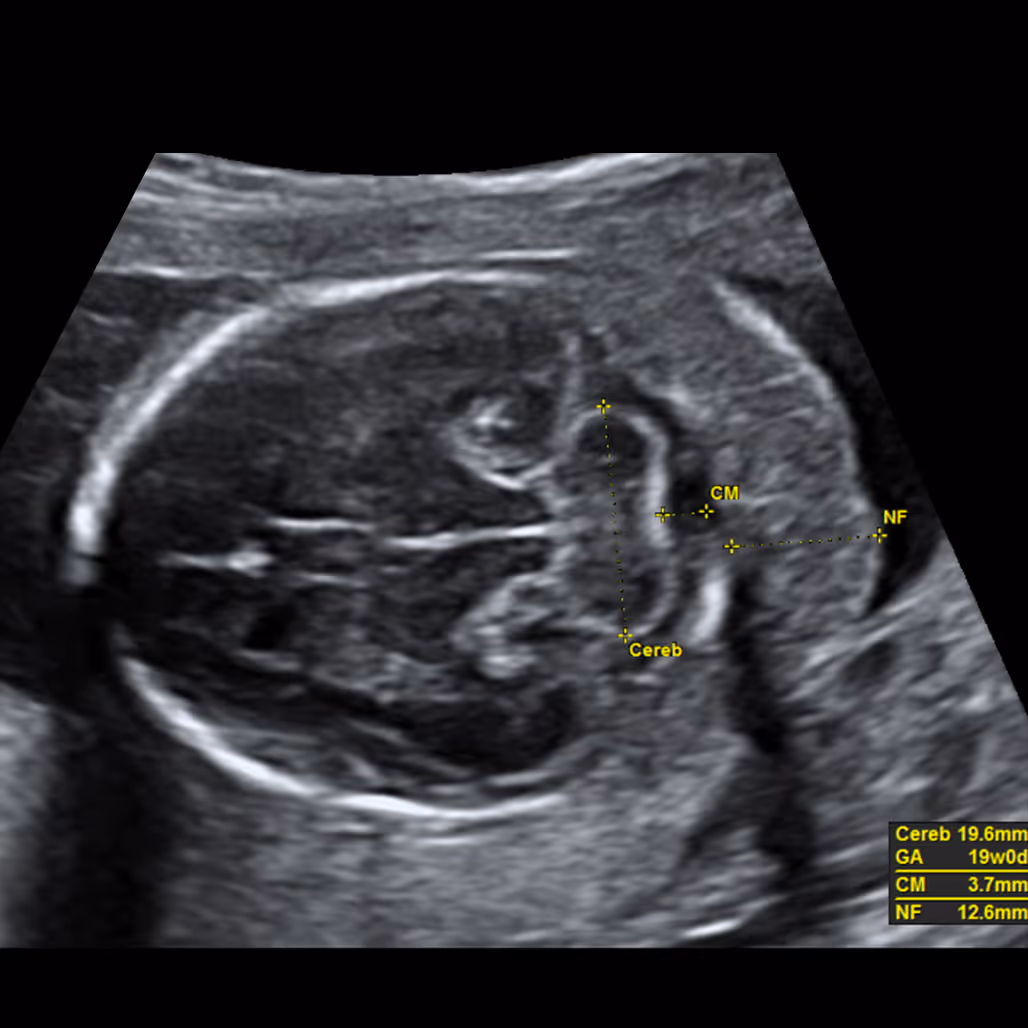

The nuchal fold (NF) is the thickness of the soft tissue (not fluid) at the back of the fetal neck. Increased NF is an ultrasound feature, not an anomaly. It was originally described by Prof Beryl Benacerraf in 1985 in the United States as the first soft marker for Down syndrome. The correct measurement of the nuchal fold in the second-trimester fetus is performed at the level of the posterior fossa, on a modified transverse view of the fetal head that includes the thalami, cerebellar hemispheres, and occipital bone. The NF is measured by placing the electronic callipers from the outer edge of the occipital bone to the outer skin surface.

An NF thickness of 6.0 mm or more is considered abnormal. This cut-off has been validated only for the period between 15 and 20 weeks of gestation. After 20 weeks, the nuchal fold naturally thickens as part of normal growth; therefore, the 6 mm threshold should be interpreted with caution.

In most pregnancies between 15 and 20 weeks, a nuchal fold measuring less than 6.0 mm is considered normal.

If your baby’s nuchal fold is 6.0 mm or more, your report will usually describe it as “increased” or “thickened”. On its own it is a soft marker, not a diagnosis, and many babies with a thick nuchal fold are born completely healthy.